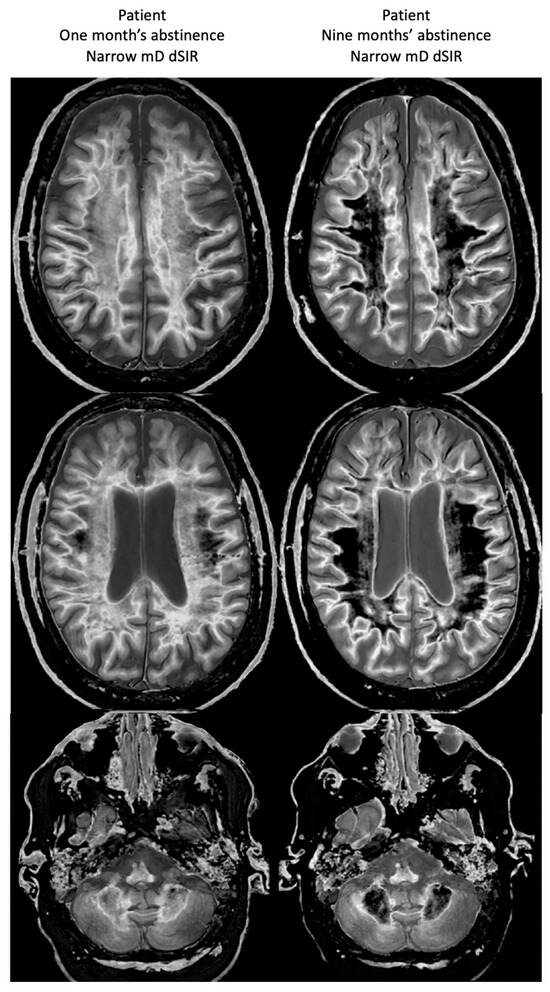

Figure 19 shows narrow mD dSIR images in the patient after one month’s abstinence (left column) and after nine months’ abstinence (right column). Extensive abnormal high signal is seen in white matter after one month’s abstinence (left column). There is marked reduction in the extent of these high signal abnormalities in white matter after nine months abstinence from whiteout sign grade 4 to grade 2 (right column). The patient clinically improved during this period.

Figure 19.

Case 1 patient with methamphetamine use disorder. Comparison of narrow mD dSIR images after one month’s abstinence (left column) and after nine months’ abstinence (right column). After one month’s abstinence the images show widespread abnormal areas of increased signal in white matter (left column). After nine months abstinence, the images show extensive dark low signal areas (right column) consistent with marked regression of his disease during the period between one and nine months’ abstinence from whiteout sign grade 4 (right column) to grade 2 (left column). The boundaries between white and gray matter as well as between CSF and white matter around the lateral ventricles become more obvious after regression of the whiteout sign.